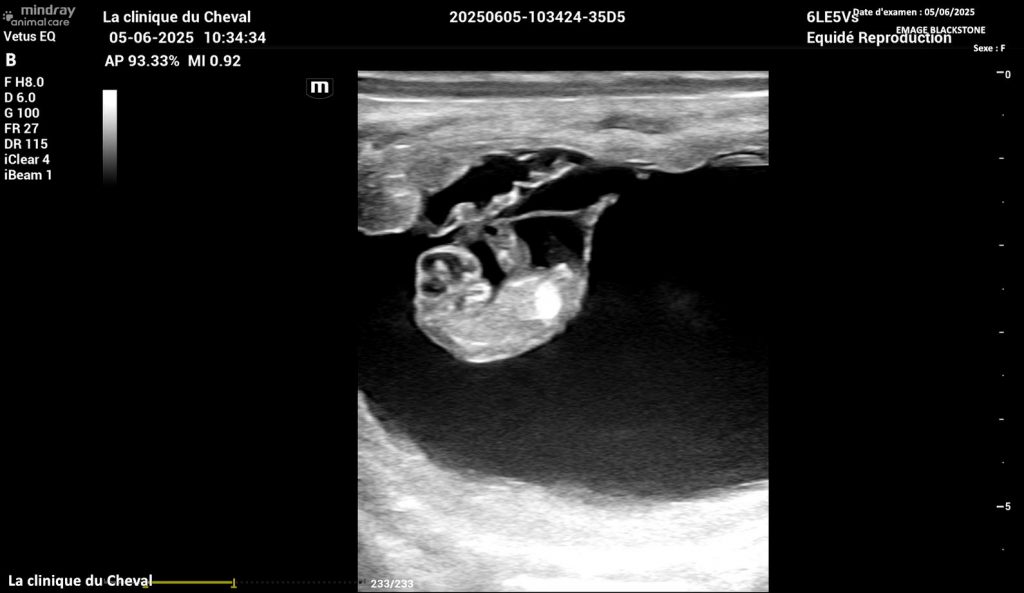

La jument de Marjorie, EMAGE BLACKSTONE, est bien confirmée pleine à 40 jours

de WESTAIRE TOLOMEO (le papa de LA TEX):

plus que 10 mois avant de découvrir cette merveille !